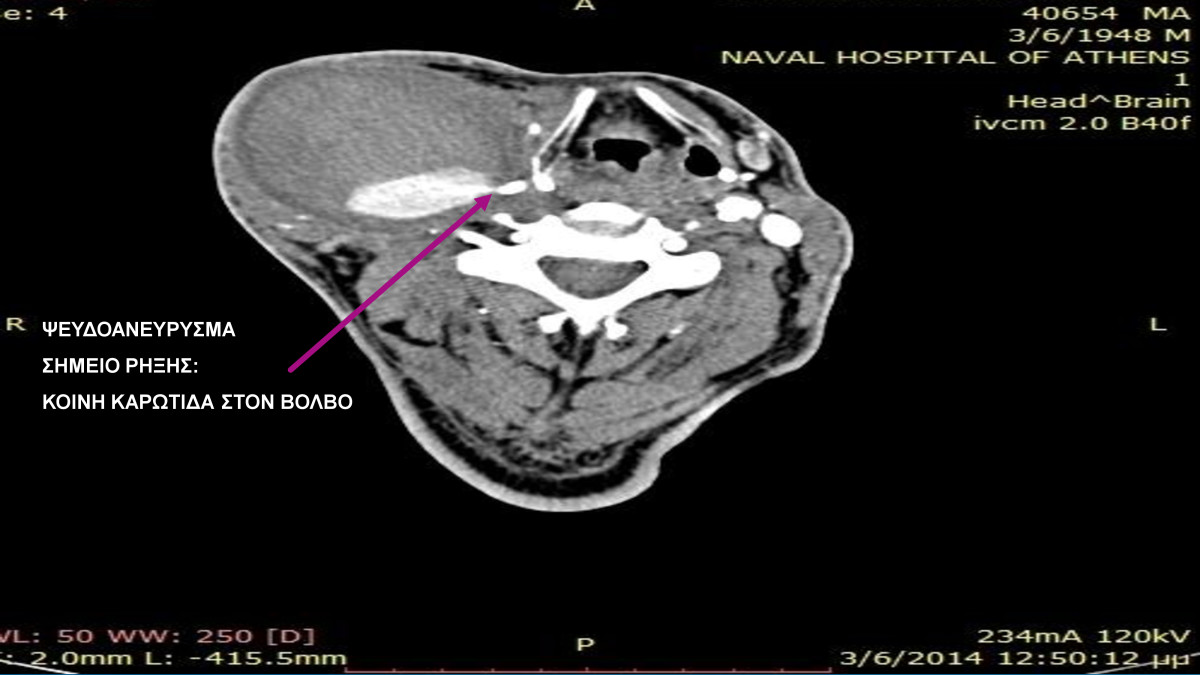

“Ενδαγγειακή Αποκατάσταση Ψευδοανευρίσματος Καρωτίδας μετα Ενδαρτηρεκτομή”

17ο ΠΑΝΝΕΛΗΝΙΟ ΣΥΝΕΔΡΙΟ ΑΓΓΕΙΑΚΗΣ & ΕΝΔΑΓΓΕΙΑΚΗΣ ΧΕΙΡΟΥΡΓΙΚΗΣ – ΑΓΓΕΙΟΛΟΓΙΑΣ

2018, Θεσσαλονίκη